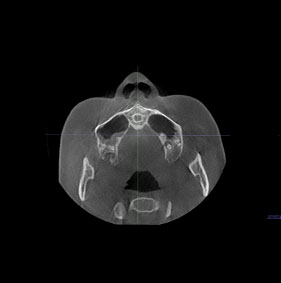

3D CT분석을 통한

정확한 코 재수술

원인 분석

코 재수술은 문제의 원인을

정확한 파악하는 것이 중요합니다.

V브이성형외과의

코성형 전담 의료진은

환자와 면밀한 상담을 통해서

현재 불만족의 원인을 파악하고

개선을 위한 방법을 모색합니다.

3D CT 분석을 통해서 해부학적인 상태를 확인하고,

기존 코수술로 인한 문제를 파악할 수 있습니다.